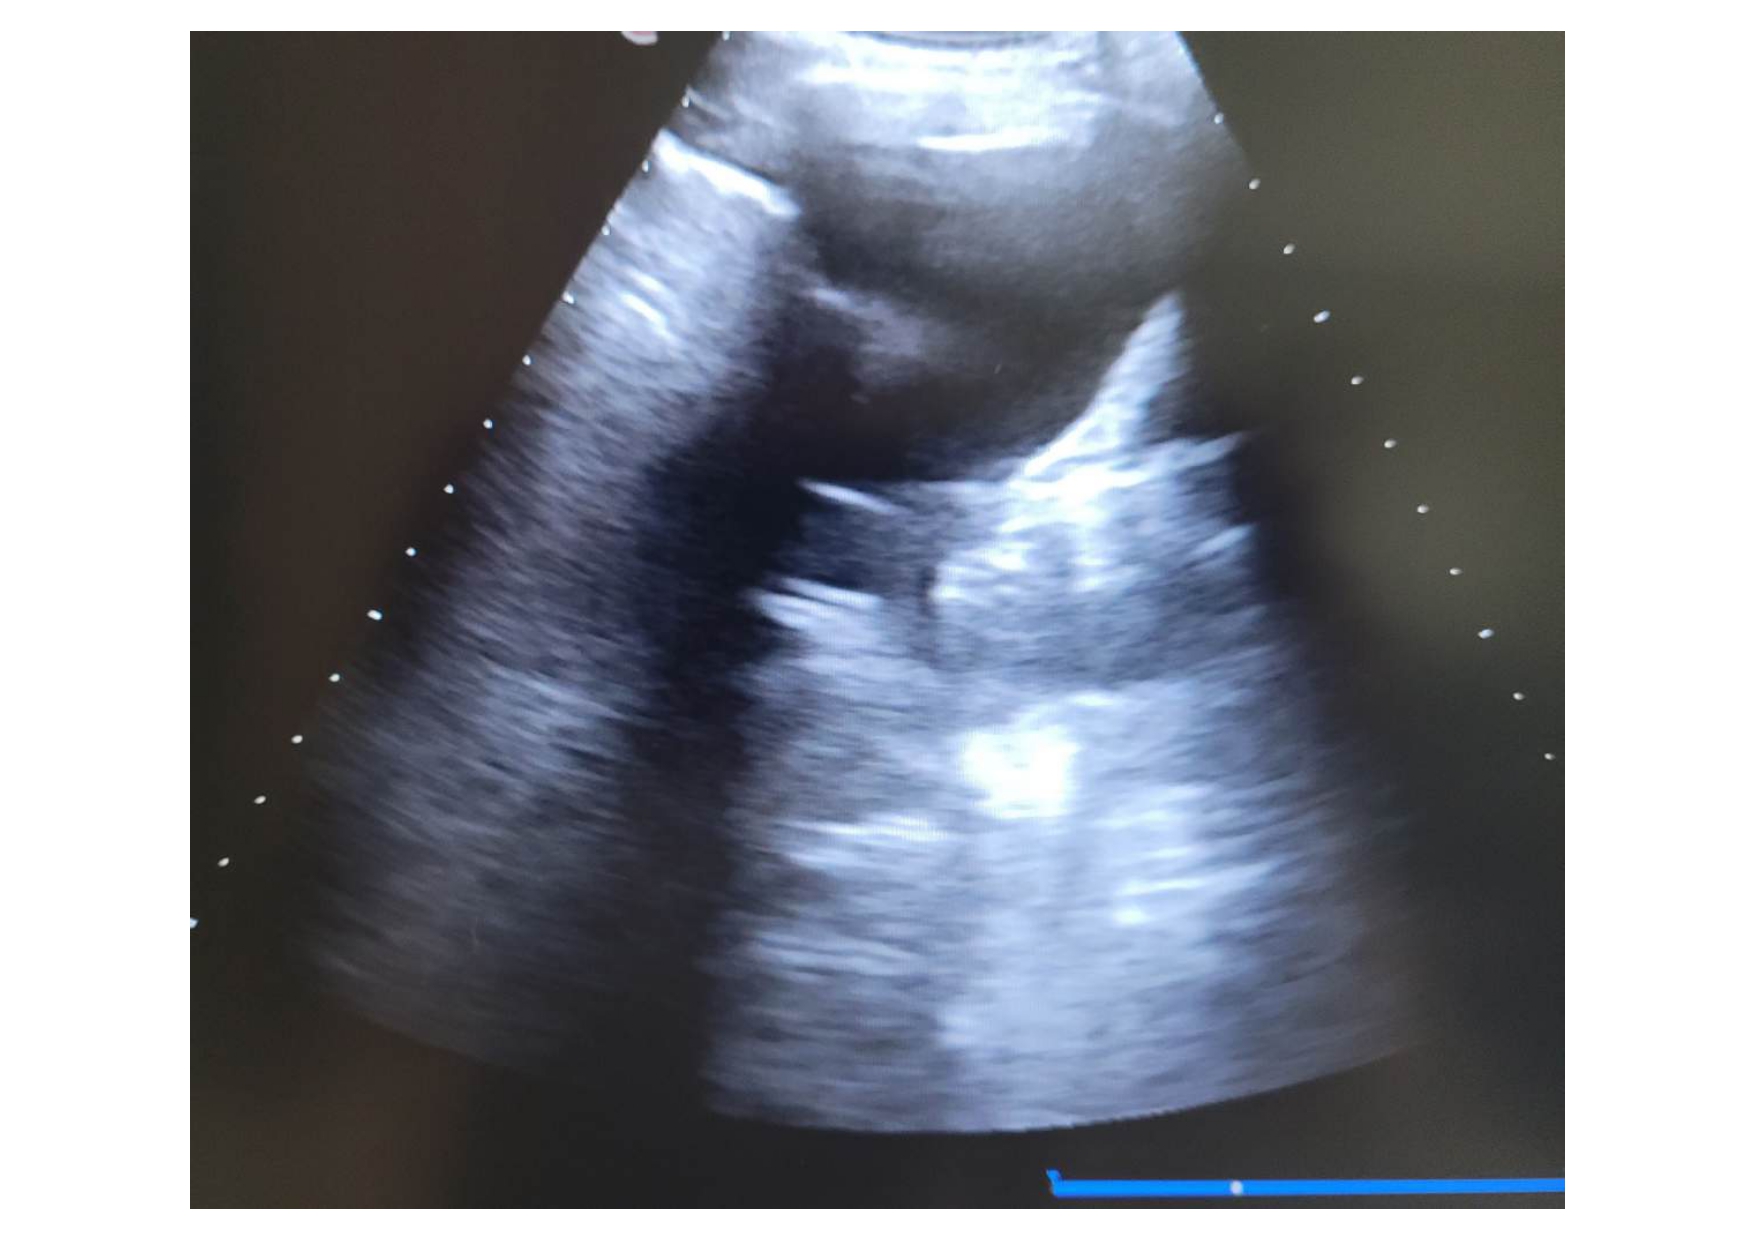

Se realiza una ecografía pulmonar, donde se observa un derrame pleural bilateral, de mayor cuantía a nivel izdo, con “signo de medusa” a ese nivel, con líneas B en áreas 6 y 12.